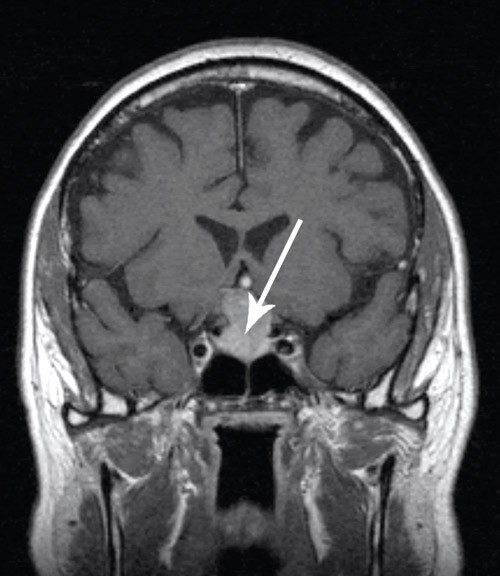

Det ble tatt MR av hypofysen, som viste et makroadenom som vokste gjennom sella turcica opp til chiasma opticum og trykte på denne. I koronalplanet var største diameter av tumoren 25 mm, i sagittalplanet største diameter 28 mm (fig 2).

Pasienten ble på bakgrunn av dette henvist til perimetriundersøkelse hos øyelege for å finne ut om tumoren påvirket synsfeltet. Dette var viktig med tanke på operasjonsindikasjonen og på hvor raskt han burde opereres. Perimetriundersøkelsen viste et lite synsfeltsutfall bitemporalt, mest uttalt på venstre øye.